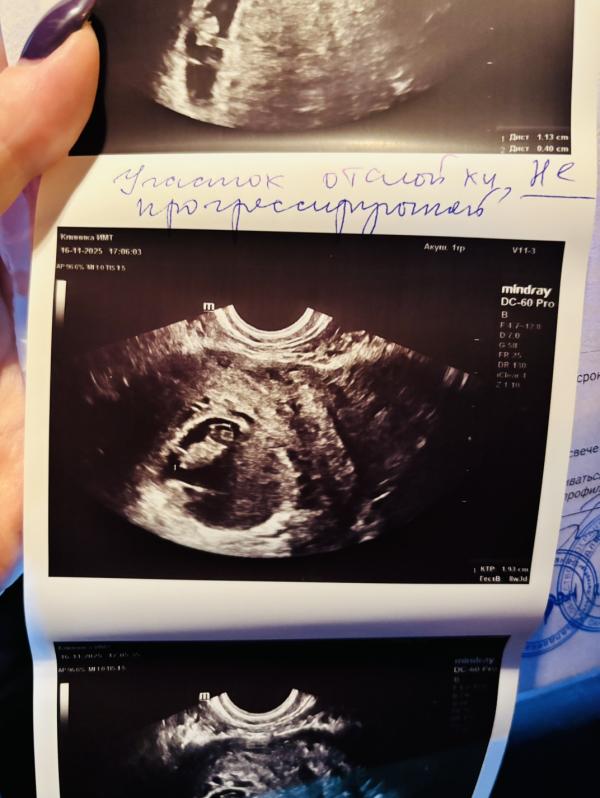

Сходила на узи из-за отслойки , боялась , что стала больше или так же .

Слава богу уменьшилась была 1,4 стала 1,1. горошинка идет в срок 8.3 как часики 🩷